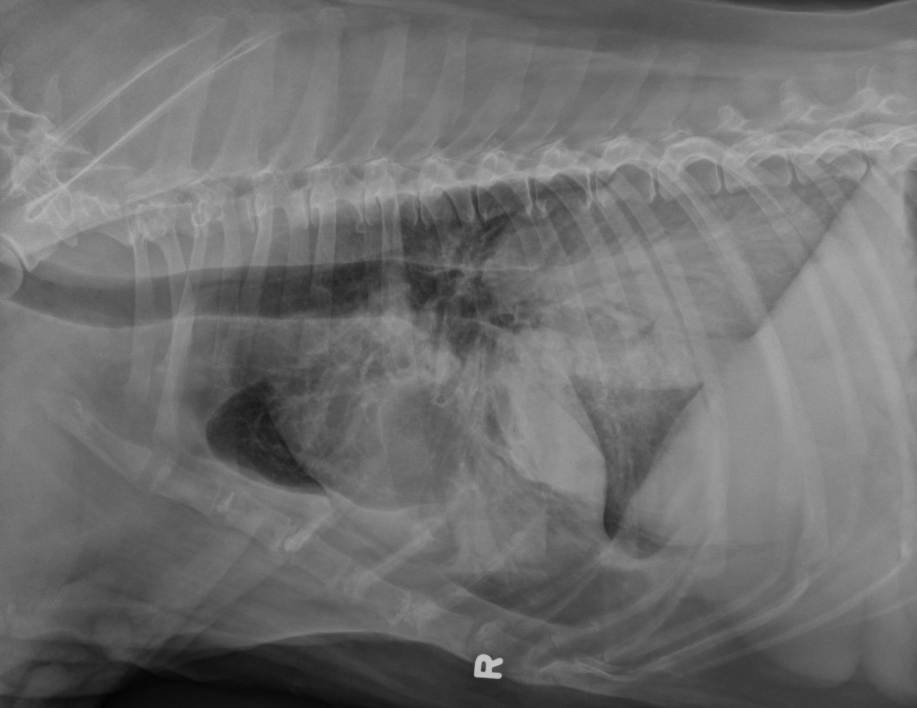

● 3 mo Bernese Mountain Dog

● Acute onset of respiratory distress and hemoptysis

● Vomited blue/purple material 10 days prior, was normal within the meantime

alveolar pattern (black trees in snow storm but blood vessels not visible)

aerophagia

bleeding into lung parenchyma secondary to rat poison ingestion